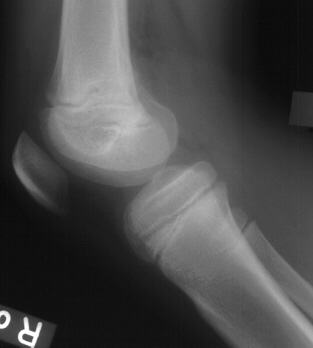

Subacute

osteomyelitis of the epiphysis maybe confused with Ewing's sarcoma, Brodie's

abscess, or osteogenic sarcoma.